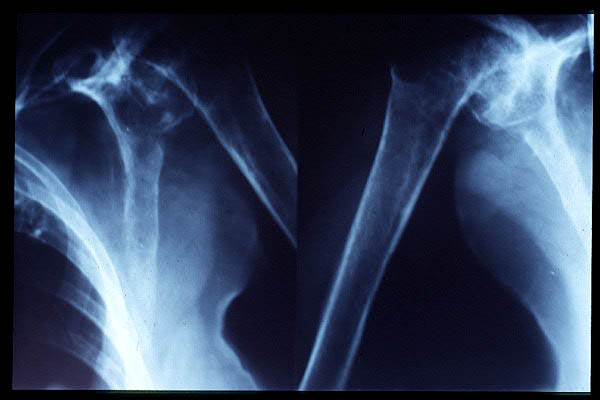

Fractura de húmero, intensa desviación de fragmentos